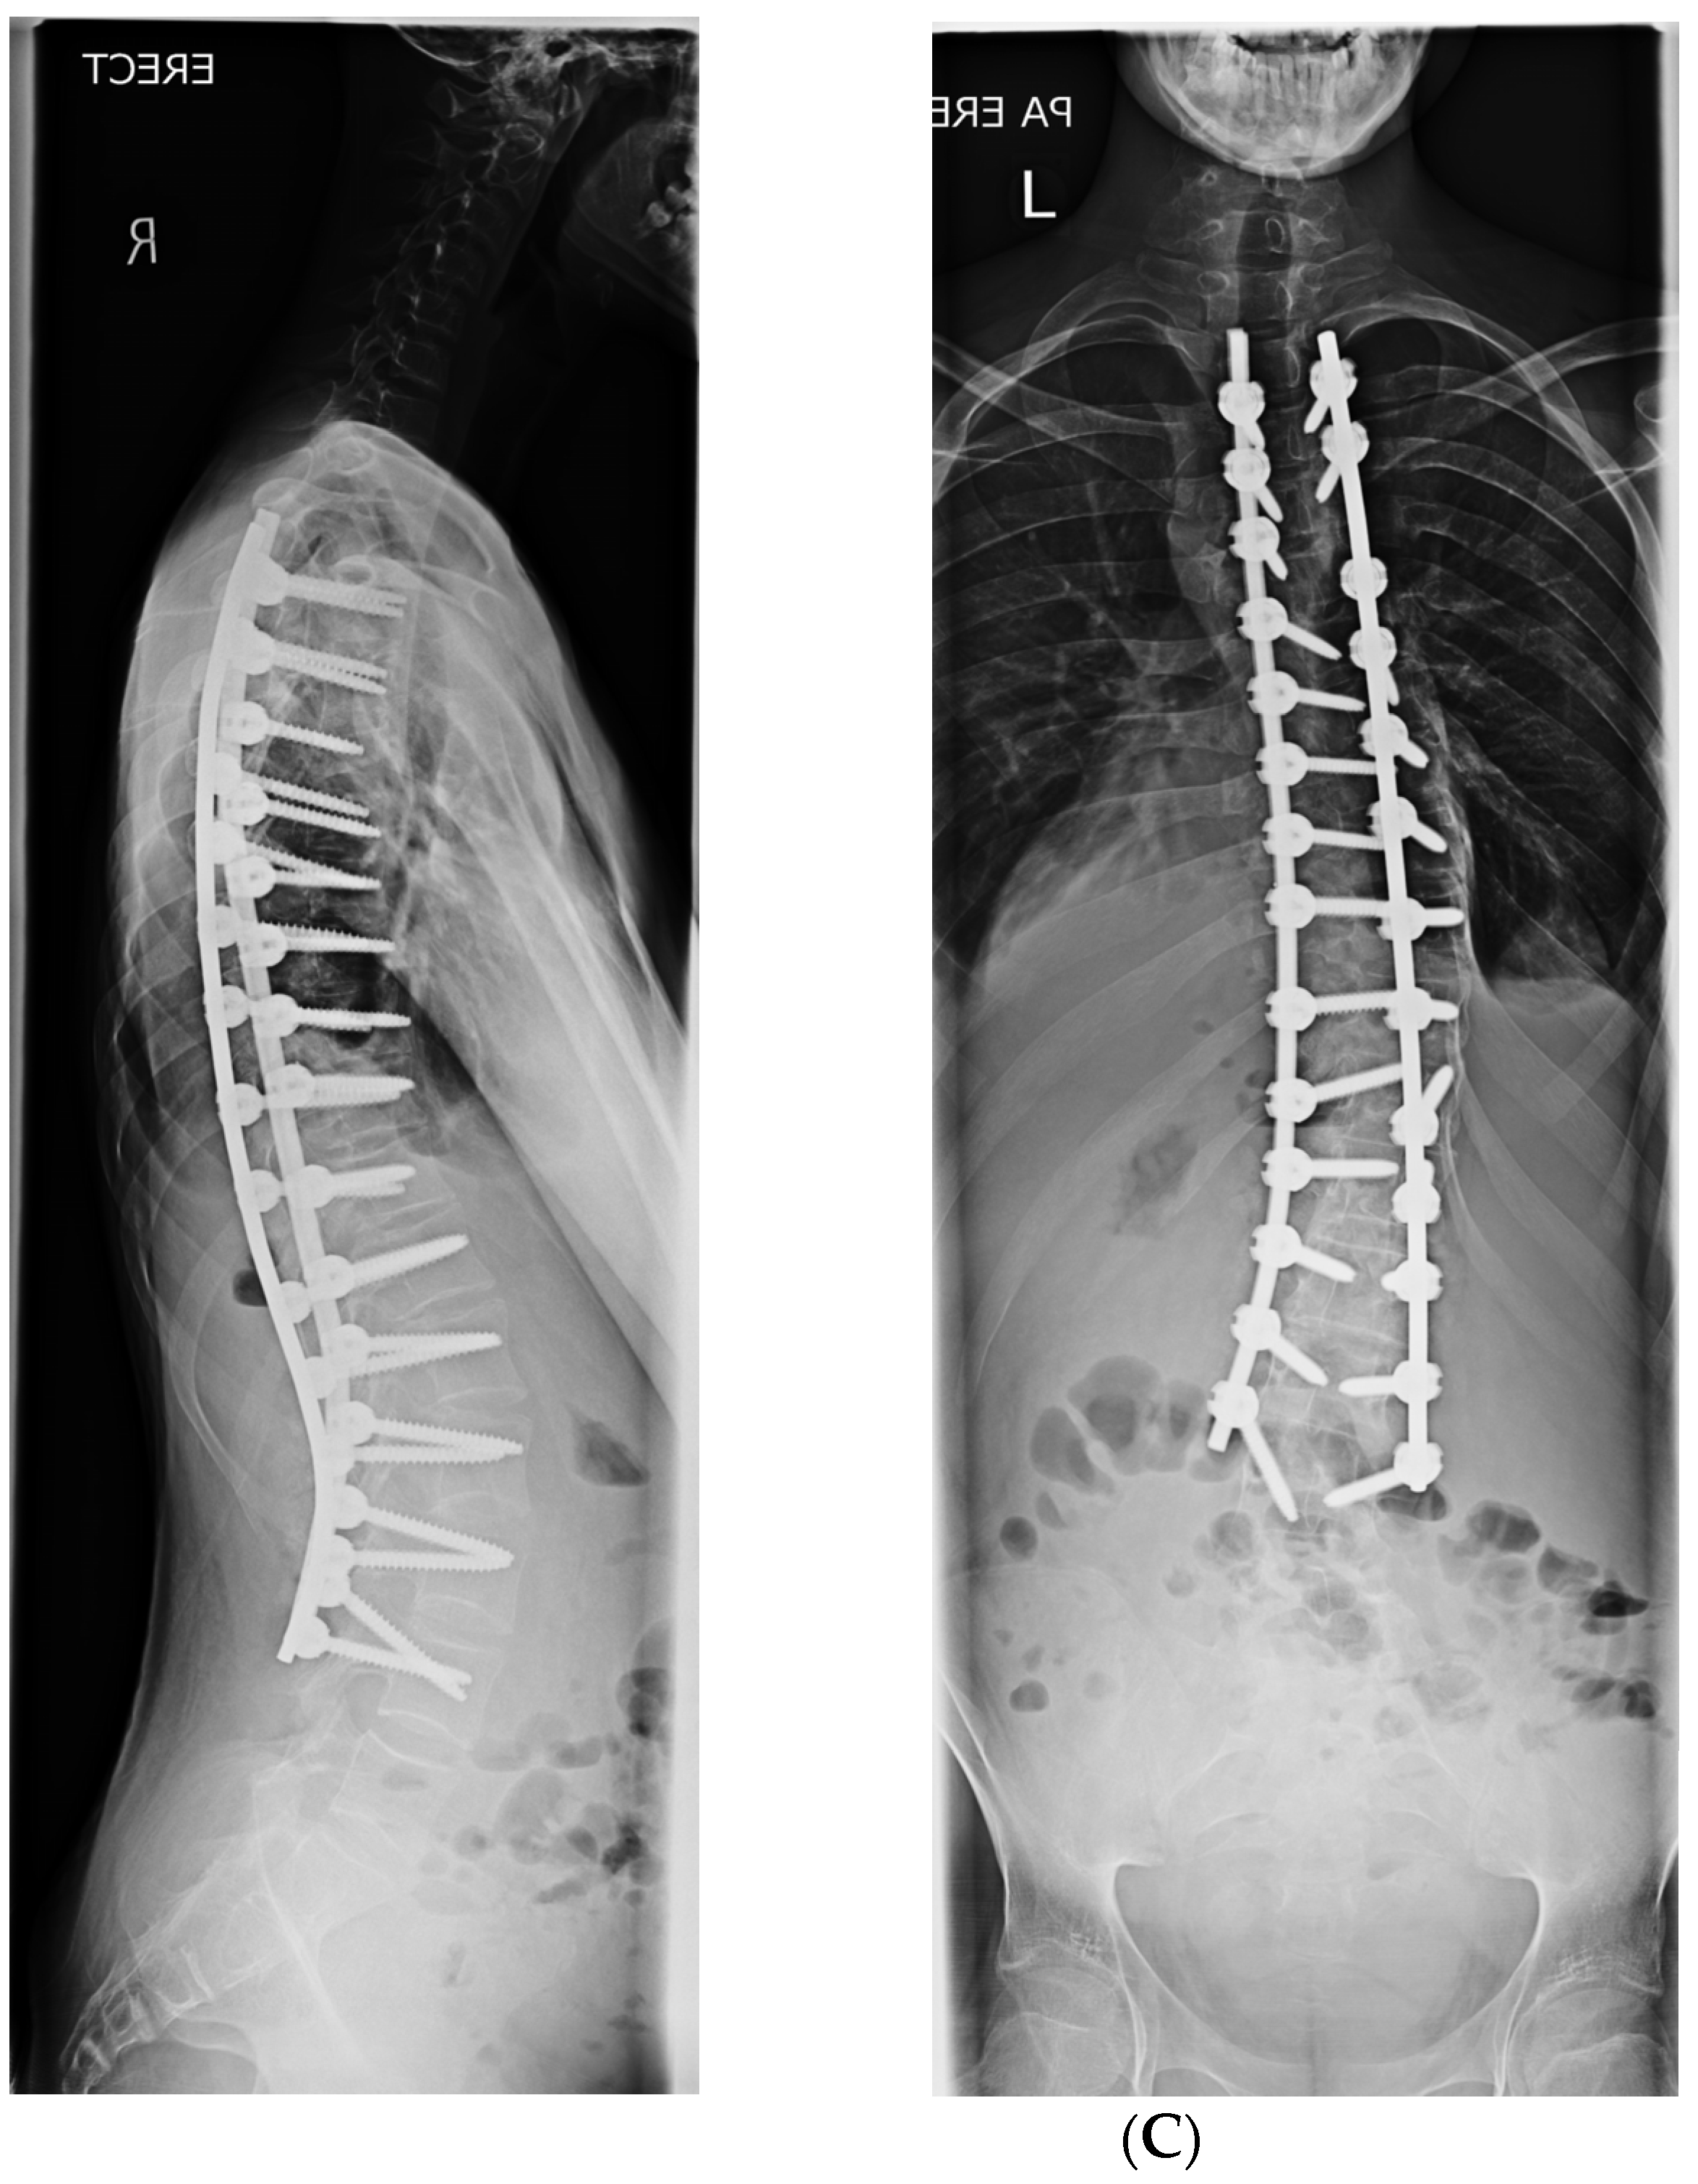

2. Materials and Methods